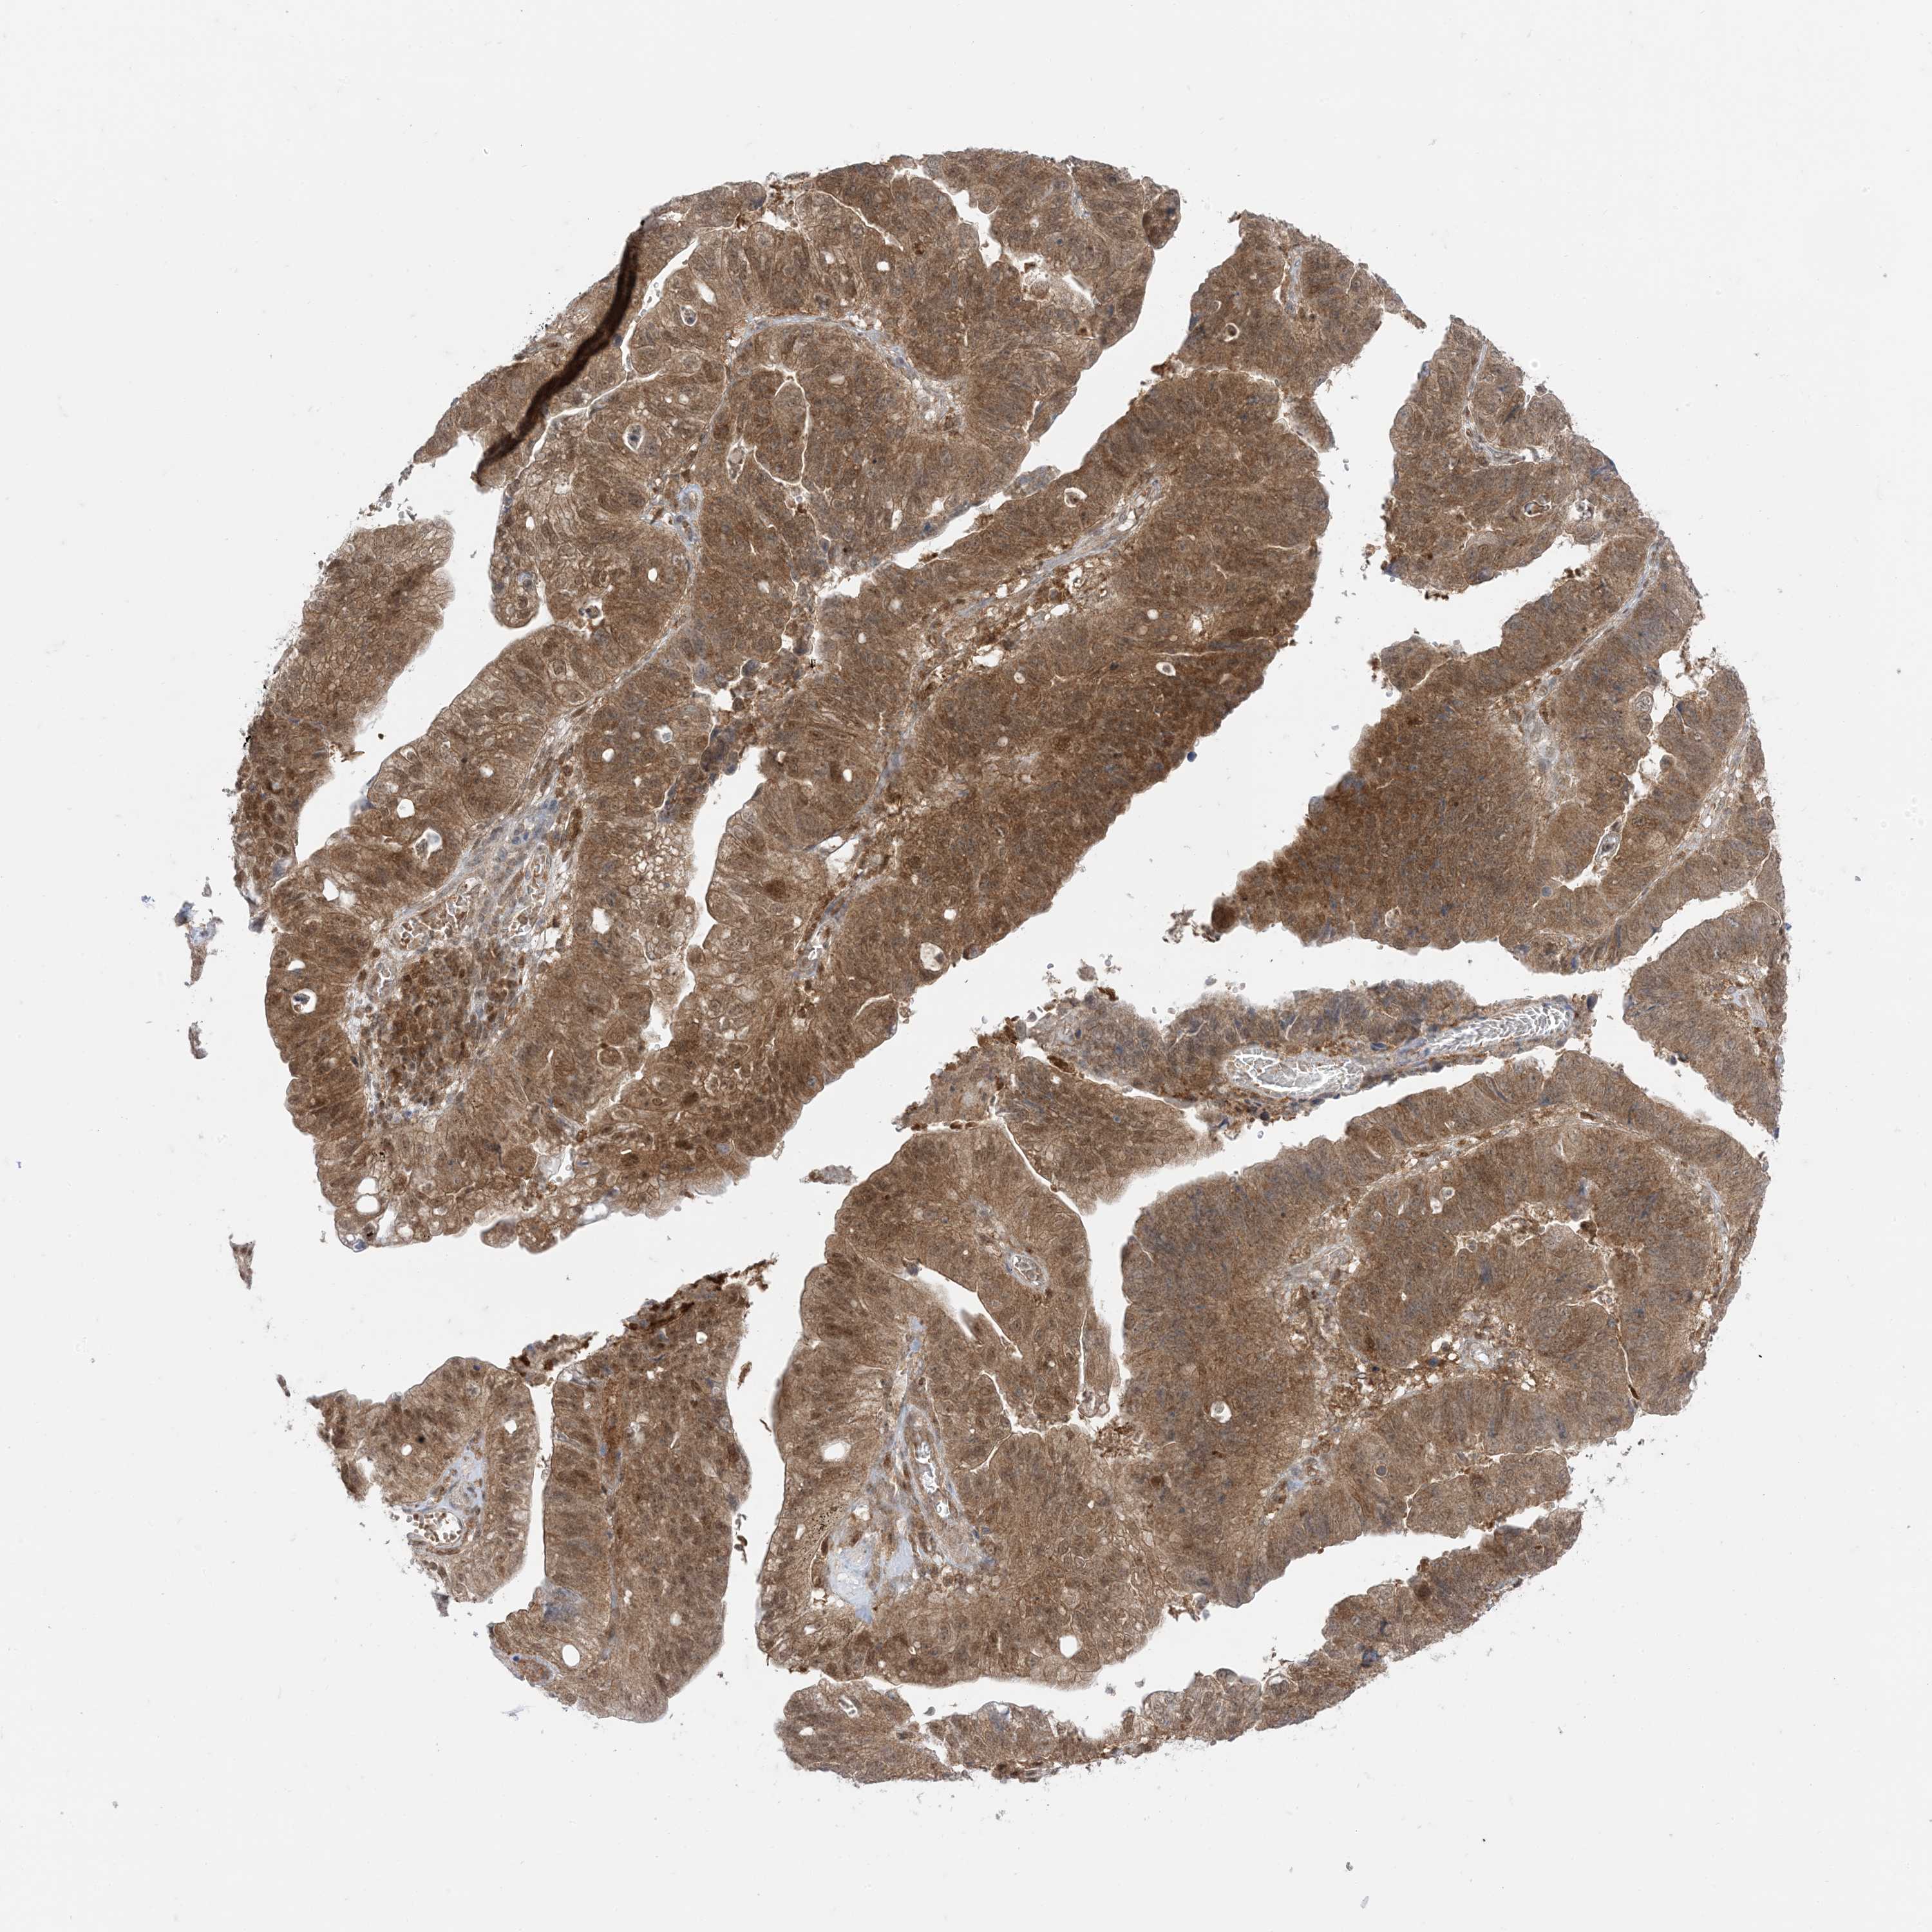

STOMACH CANCER - Protein expressioni

A mouse-over function shows sample information and annotation data. Click on an image to view it in a full screen mode. Samples can be filtered based on level of antibody staining by selecting one or several of the following categories: high, medium, low and not detected. The assay and annotation is described here.

Note that samples used for immunohistochemistry by the Human Protein Atlas do not correspond to samples in the TCGA dataset.

Antibody stainingi

Antibody staining in the annotated cell types in the current human tissue is reported as not detected, low, medium, or high, based on conventional immunohistochemistry profiling in selected tissues. This score is based on the combination of the staining intensity and fraction of stained cells.

Each image is clickable and will lead to virtual microscopy that enables deeper exploration of all samples and also displays staining intensity scores, fraction scores and subcellular localization as well as patient and tissue information for each sample.

HPA005695

CAB022068

CAB035999

CAB080052

CAB080054

CAB080098

Staining

High

Medium

Low

Not detected

Intensity

Strong

Moderate

Weak

Negative

Quantity

>75%

75%-25%

<25%

None

Location

Nuclear

Cytoplasmic/membranous

Cytoplasmic/membranous,nuclear

Adenocarcinoma, NOS

Adenocarcinoma, High grade